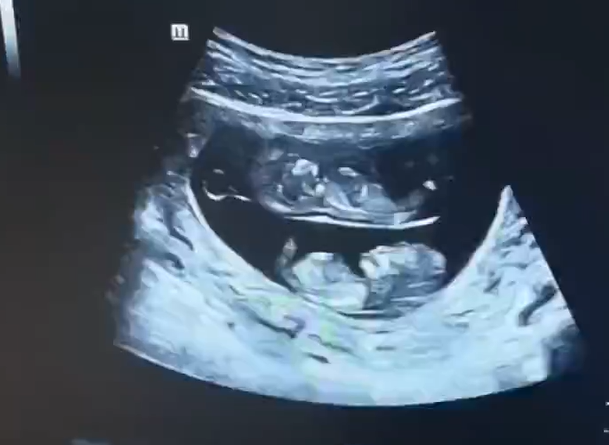

孕妇做B超拍到上下铺宝宝 网友:真·睡在我上铺的兄弟

9月3日,河南的一位孕妇妈妈晒出了一对双胞胎宝宝的B超照片,简直逗笑了一群人!这对宝宝的B超图画风有点不一样哦。

首先,让我们来欣赏一下这对萌萌哒的双胞胎?;嫔?,有两颗宝宝的小脑袋,一颗在上面,一颗在下面,就像是他们自己在母亲的肚子里订了上下铺一样。当这张照片被晒出后,网友们纷纷惊呼:“原来双胞胎还有上下铺啊,还以为都是大通铺!” 看来大家对于双胞胎的构造有了全新的认识!